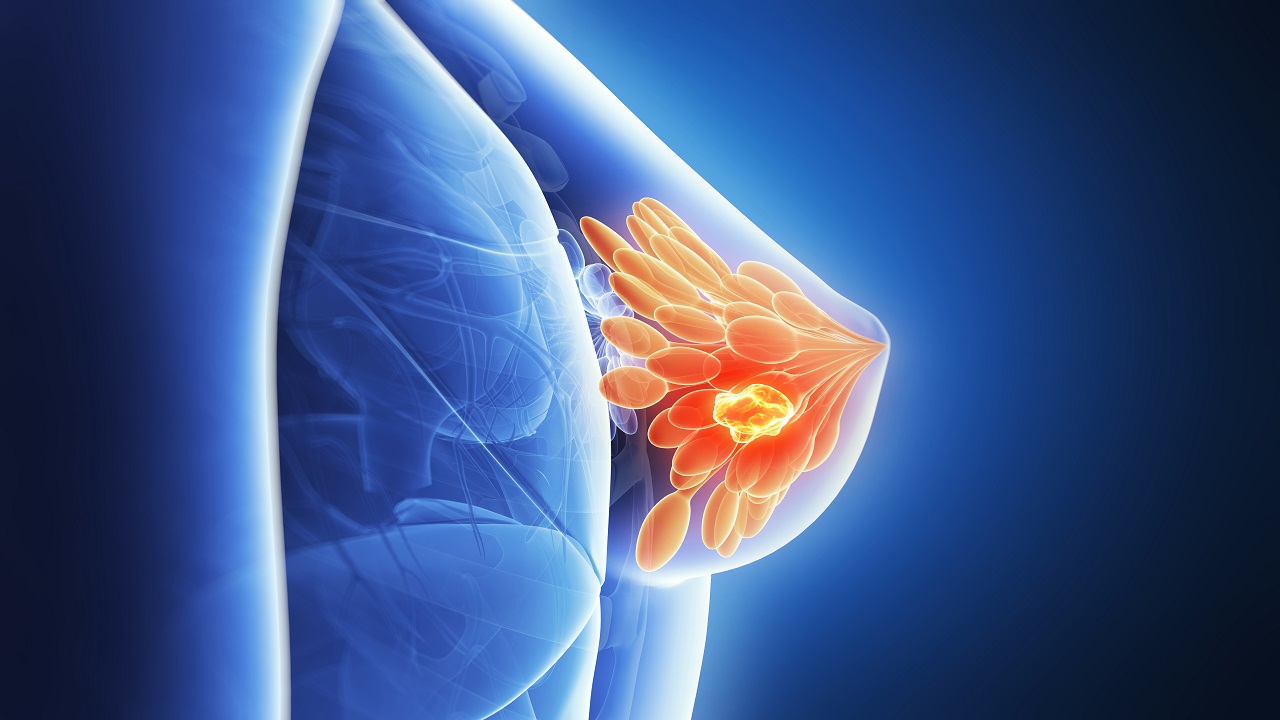

Oncology

Oncology is the study of cancer. An oncologist is a doctor who treats cancer and provides medical care for a person diagnosed with cancer.